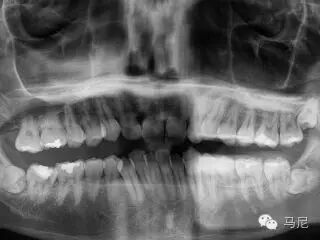

拔牙前的风险和难度预判非常重要。术者需要在拔牙前应针对病人主诉问题进行详细口内检查、仔细确认所需拔除的牙齿,了解患牙情况及其与邻牙、周围组织的关系。所有患者常规均应行术前X线片检查,对于根尖片无法满足手术需要的病例,则需进一步拍摄牙科CT,了解牙齿形态、结构及与周围重要解剖结构(如上颌窦、下颌神经管等)的位置关系。术前与患者及家属进行良好的交流和沟通,交代拔牙术过程及术中、术后的相关事项,以缓解患者的紧张、恐惧心理,取得其信任与配合。对于高度紧张或牙科恐惧症患者,术前应采用镇痛、镇静等措施,以达到心理、精神的微创。此外,根据术前预判和设计,准备合适的微创拔牙器械。

难易度最高的深埋横卧智齿